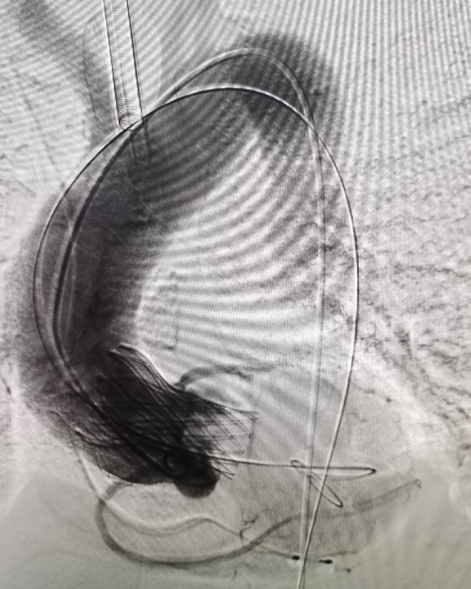

主动脉根部造影

导丝跨瓣

球囊预扩

输送器过弓

输送器定位

瓣膜定位

瓣膜脱钩

全息剪影